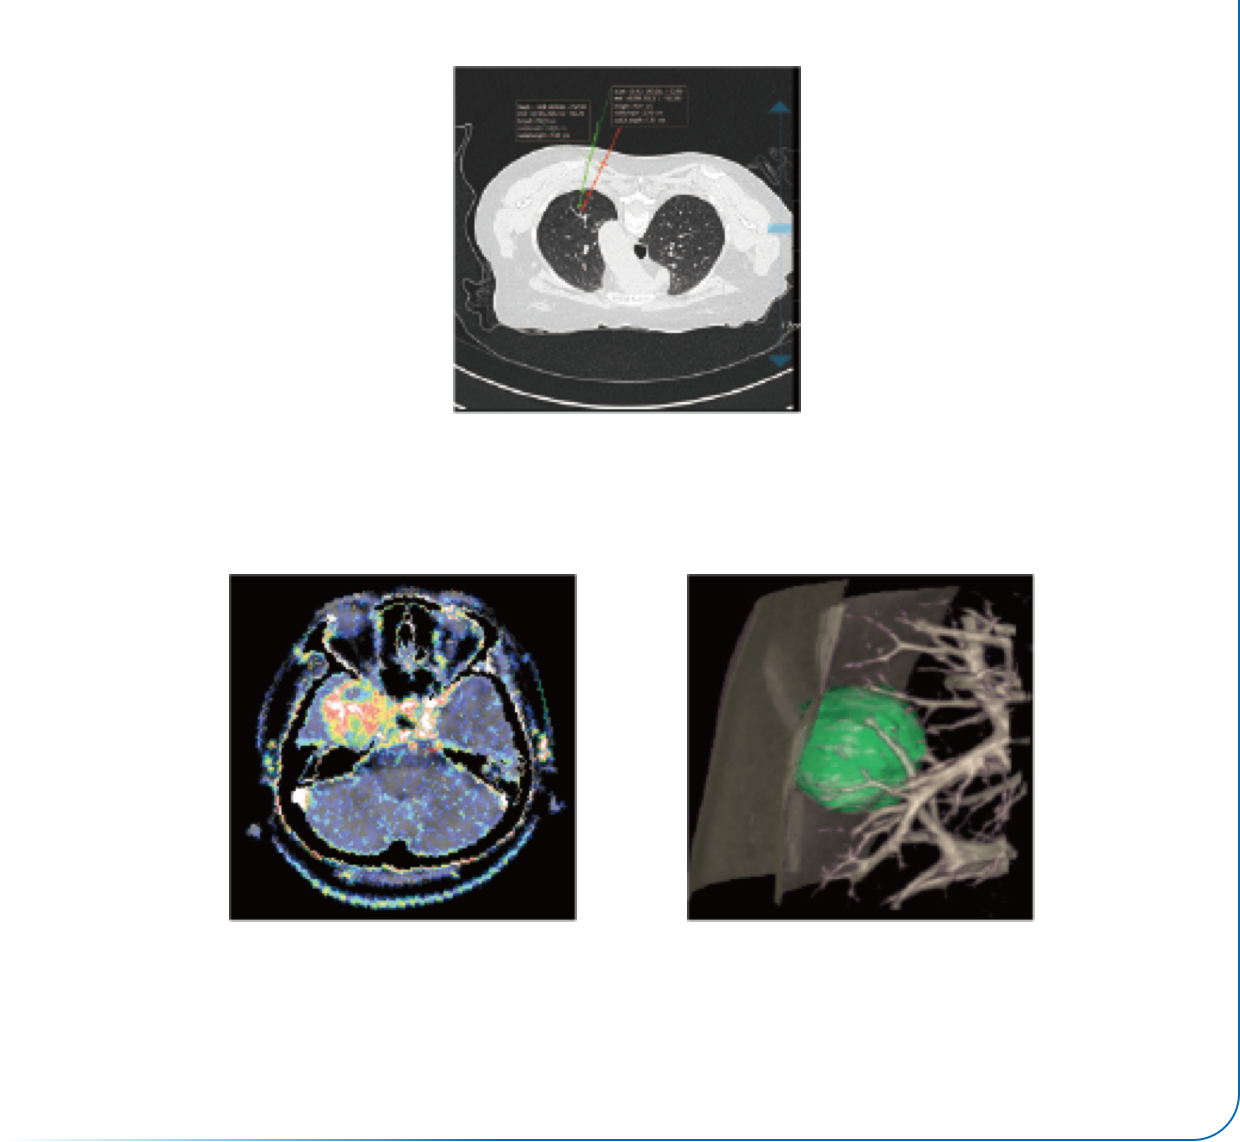

低kV成像技术

智能全域迭代iDream

智能剂量预警